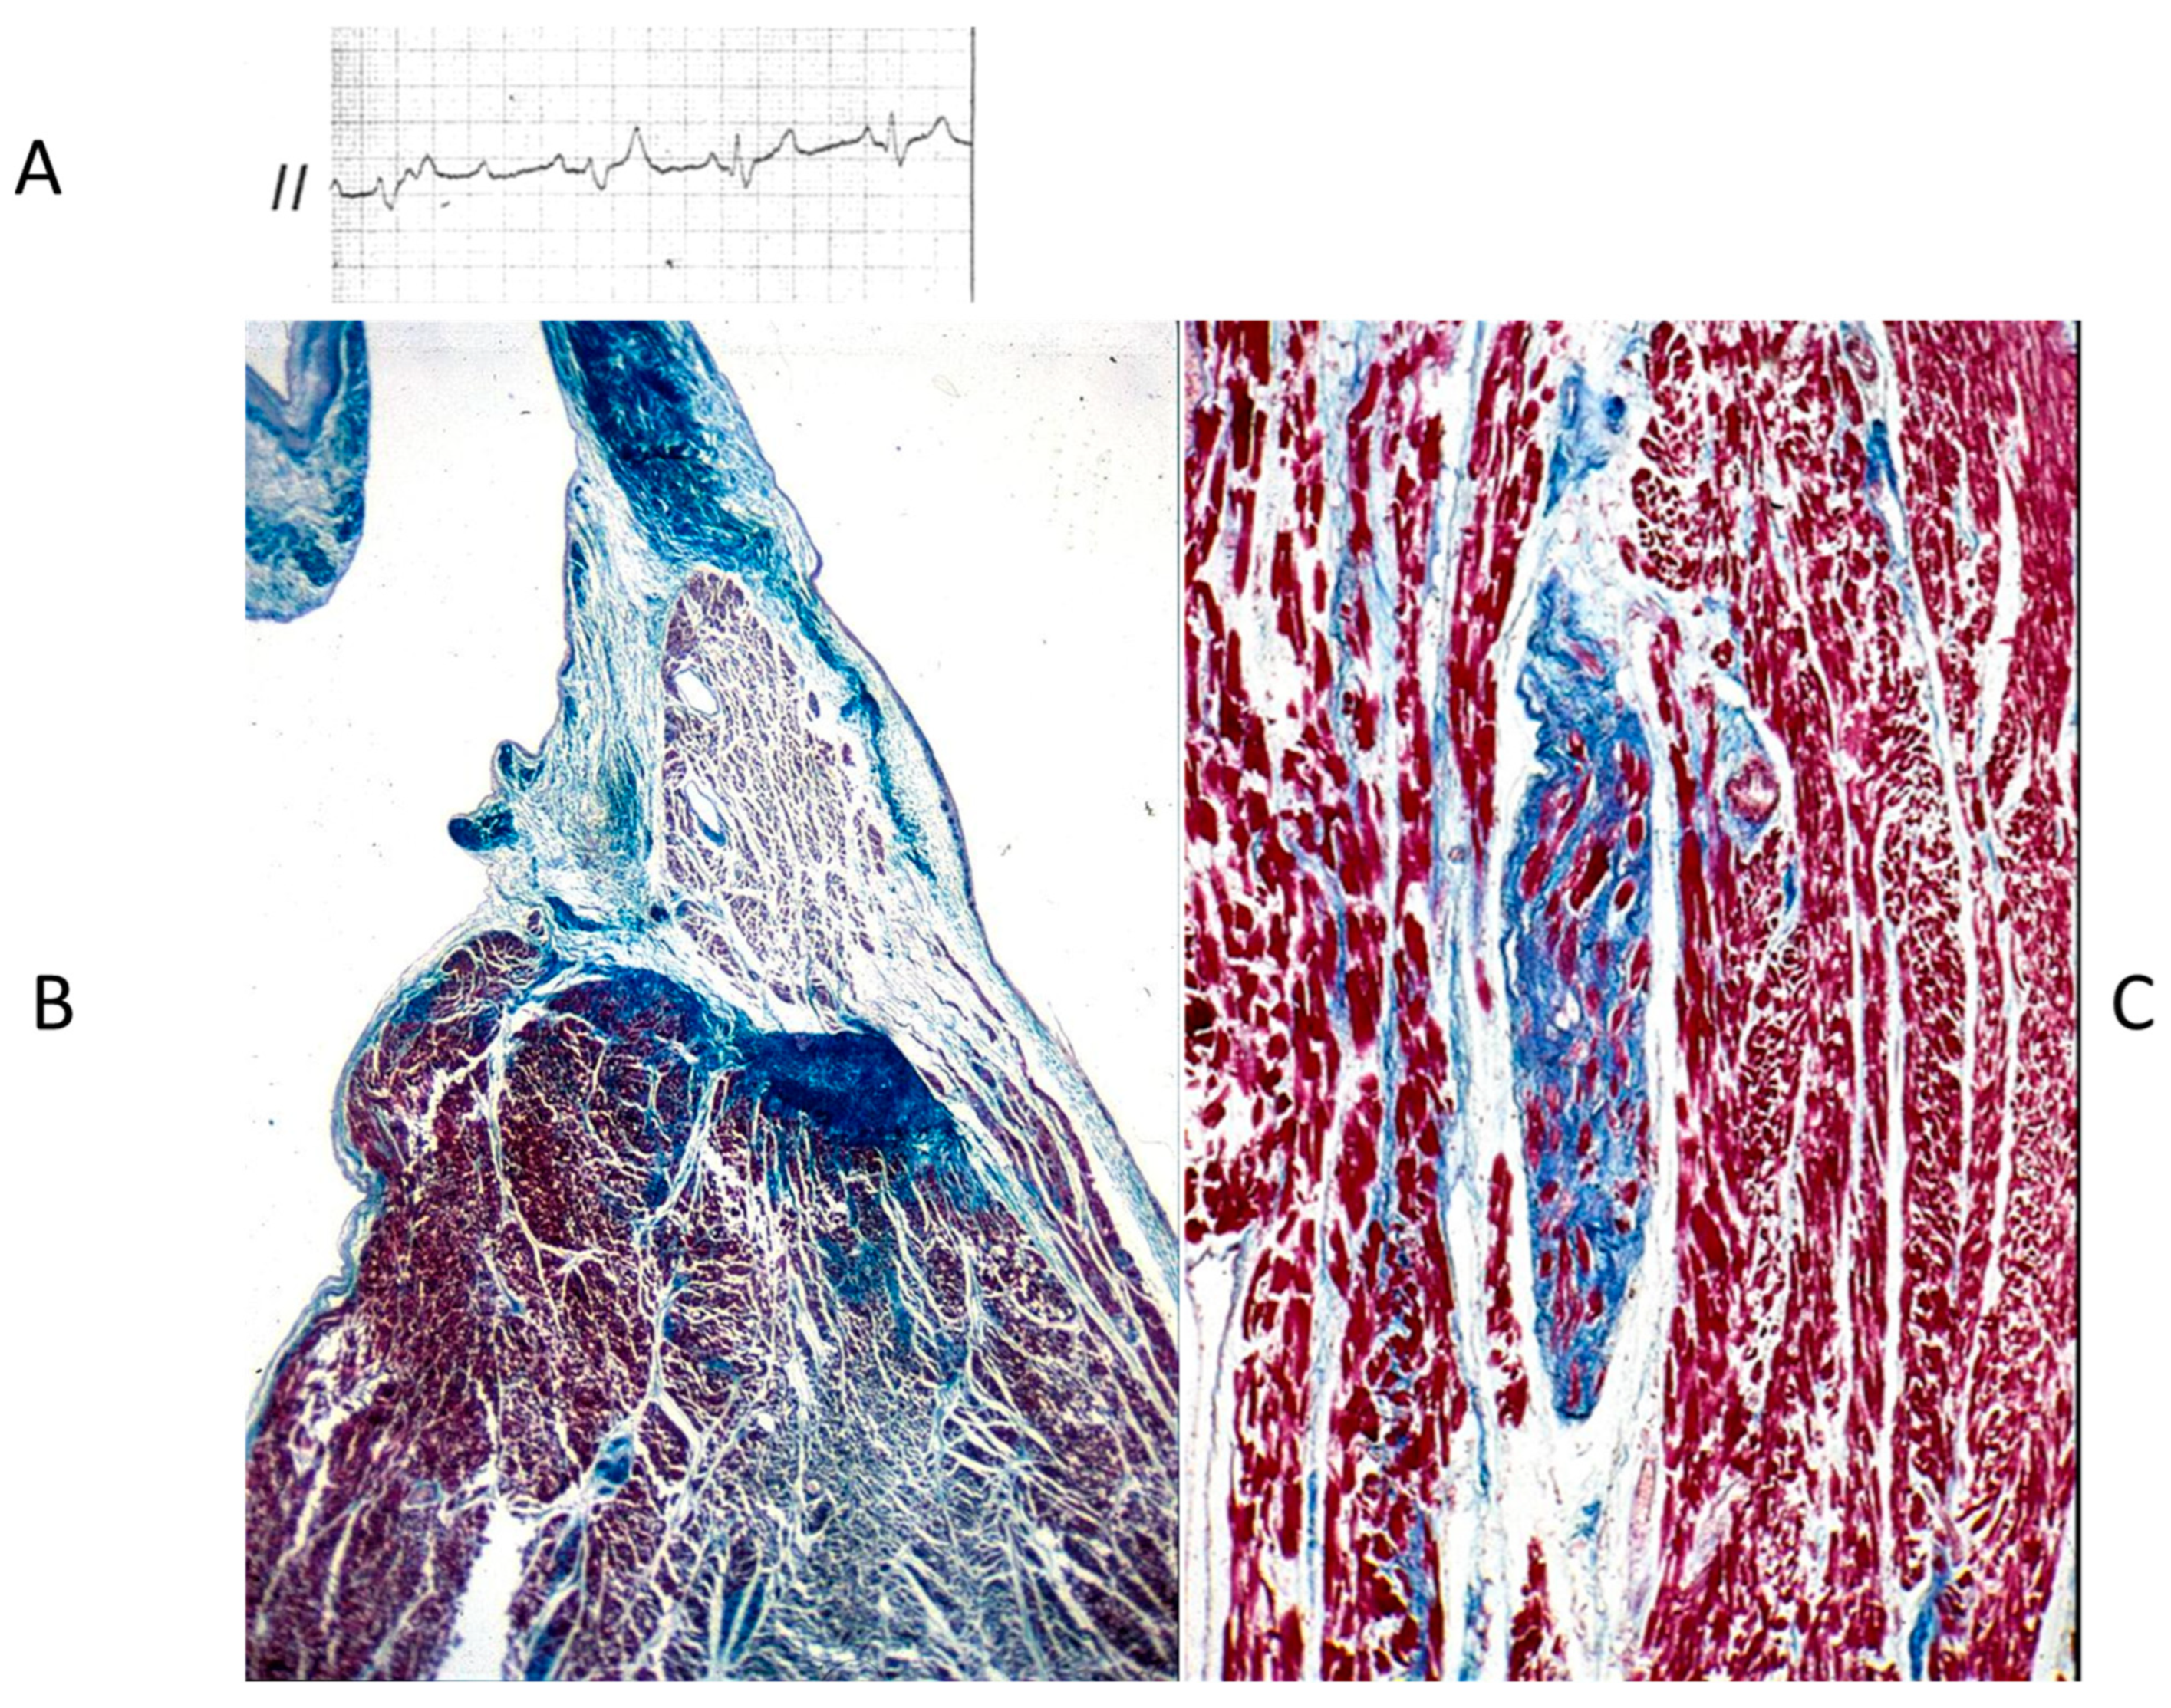

The Ebstein anomaly [20,21,22], with lowering of the leaflets and incompetence of the tricuspid valve (Figure 12 and Figure 13), is associated with myocardial dystrophy of the right ventricle free wall (Figure 14) and with ventricular preexcitation (Figure 15).

Figure 12.

Ebstein anomaly with downward displacement of the tricuspid valve leaflets (A). Note a porcine bioprosthetic valve in place of the tricuspid valve (B) [9]. RV = right ventricle [20].

Figure 14.

Aneurysm by dystrophy of the right ventricular wall (B) in an adult patient with Ebstein anomaly of the tricuspid valve (A). RA = right atrium; RV = right ventricle.